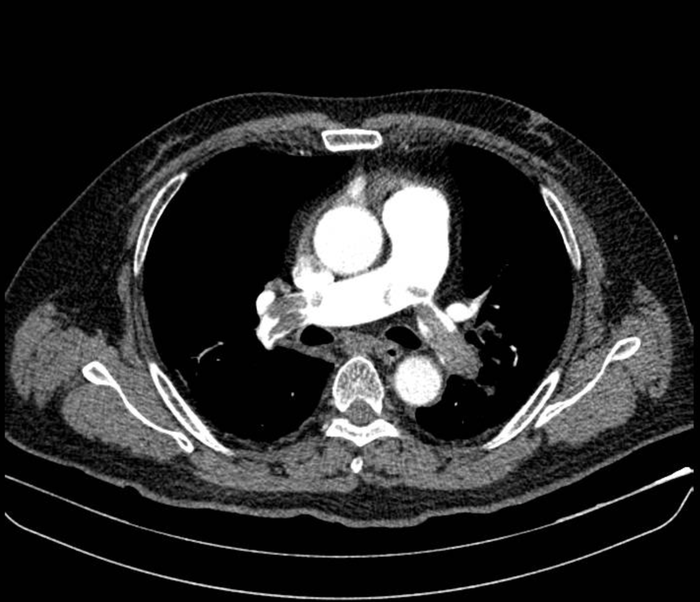

Người bệnh được nhanh chóng sử dụng thuốc vận mạch nhằm ổn định huyết áp và đưa đi chụp cắt lớp vi tính (CT) mạch máu phổi với kết quả: huyết khối lớn bít tắc động mạch phổi hai bên. Với sự phối hợp của bác sĩ khoa Hồi sức tích cực, người bệnh được xác định chẩn đoán sốc tắc nghẽn do thuyên tắc phổi nguy cơ cao.

Hình ảnh chụp cắt lớp vi tính mạch máu phổi cho thấy huyết khối lớn bít tắc động mạch phổi hai bên